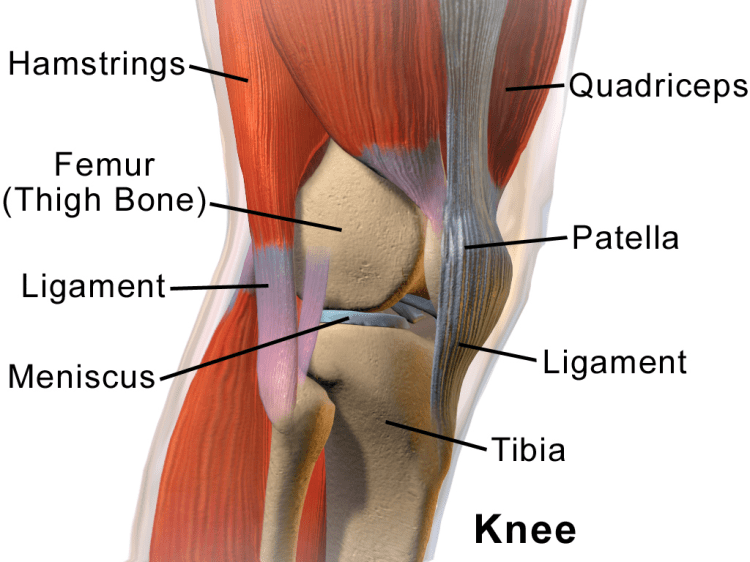

L’anatomie du genou.

Le genou est la jonction du fémur, du tibia et de la patella (rotule). Il contient deux cartilages ménisques (médiale qui se trouve à l’intérieur du genou et latérale qui se trouve à l’extérieur), qui absorbent le choc du mouvement, et le cartilage hyalin articulaire (dans le fémur, au-dessus du tibia et juste derrière la patella), qui assure le mouvement des os sans créer de friction. Quatre ligaments connectent ces différents os du genou et amènent la stabilité :

- LCA ou ligament croisé antérieur, qui empêche le fémur de glisser vers l’arrière sur le tibia et le tibia de glisser vers l’avant sur le fémur.

- LCP ou le ligament croisé postérieur, qui empêche le fémur de glisser vers l’avant sur le tibia et le tibia de glisser vers l’arrière sur le fémur.

- Le ligament collatéral tibial qui empêche le mouvement latéral du fémur.

- Le ligament collatéral fibulaire qui aide aussi à empêcher le mouvement latéral du fémur.

Les divers tendons, dont le tendon patellaire (qui connecte la patella aux quadriceps), connectent le genou aux quadriceps (les 4 muscles qui permettent de redresser le genou) et aux ischios-jambiers (les trois muscles qui permettent la flexion du genou). Le liquide synovial assure la lubrification du genou. Et bien qu’ils ne soient pas directement liés, les muscles glutéaux impactent l’alignement du genou.